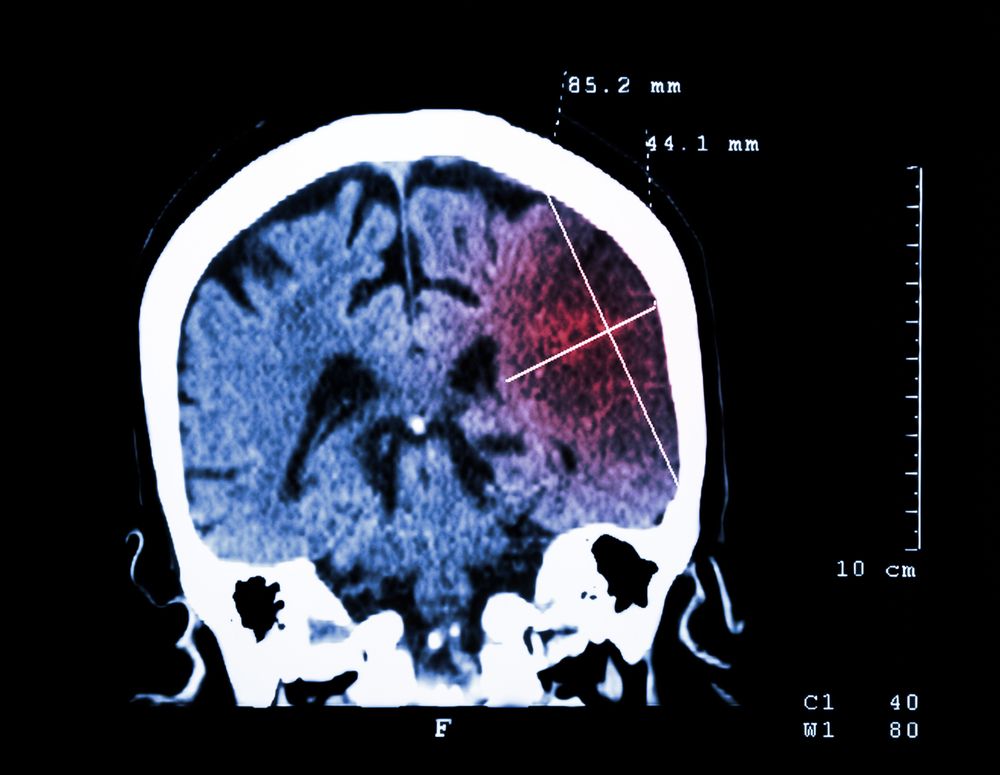

Intravenous alteplase (tPA) is the standard of care for acute ischemic stroke, if it can be given within 3-4.5 hours after stroke onset. Dr. Wilner reviews some important facts about intracranial hemorrhage after the use of intravenous alterpase.